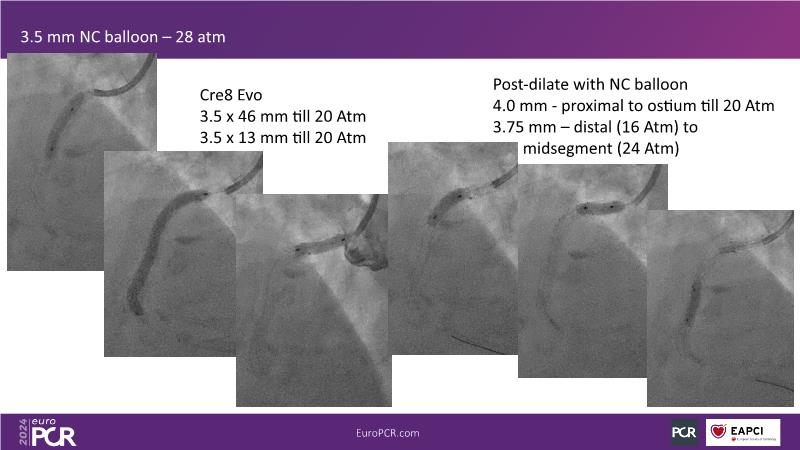

From innovation to reality: the impact of Cre8 EVO technology on complex PCI

This session is a good opportunity to delve into the contemporary technical and clinical complexities surrounding complex PCIs in challenging patient cases. Explore the necessary tools and treatment strategies to enhance peri-procedural and long-term clinical outcomes, and follow discussions on the unique technologies of Cre8 EVO in complex PCI scenarios.